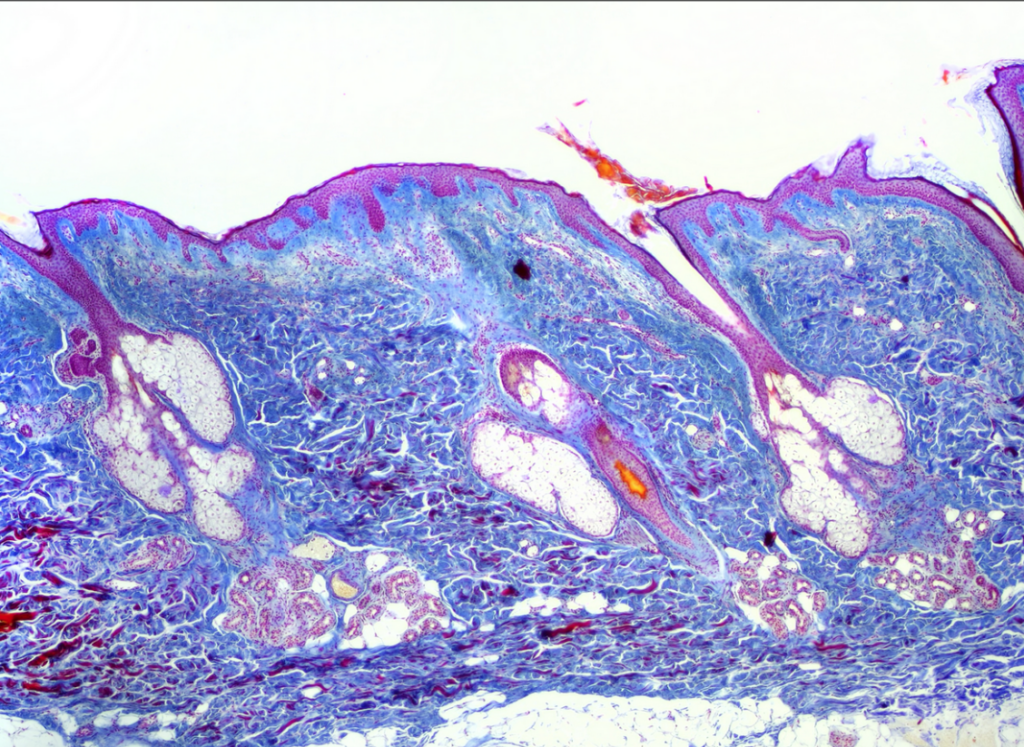

- Skóra owłosiona (skóra cienka)